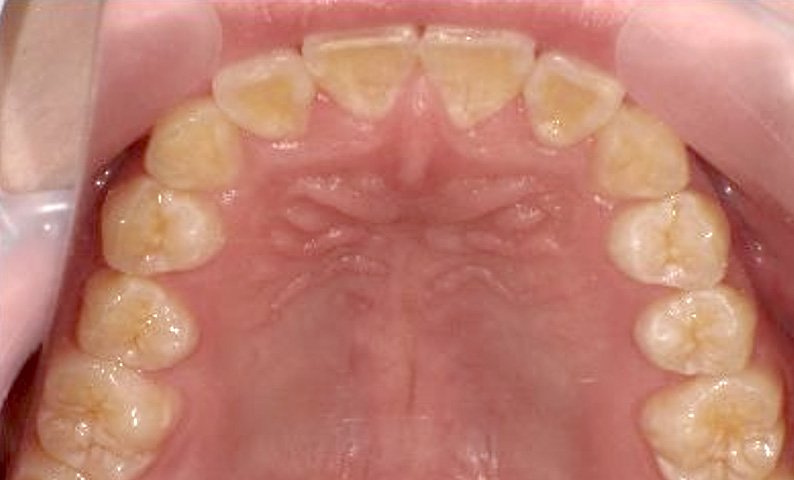

症例_024 上下顎の部分矯正

治療期間:13ヶ月金額:51万円+税女性前歯のガタガタ八重歯